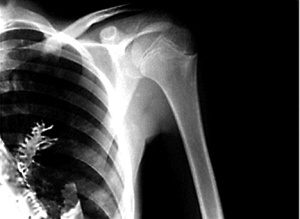

2009年 , 一名28岁的小伙子 , 因为肺部异常的疼痛来到当地的癌症中心进行检查 。 在经过X光检查后 , 他被诊断为肺癌 。 随后当地的医生为他进行了外科手术 , 当打开小伙的肺部时发现他的肺上竟然长着很多针状的绿色树叶 。 仔细一看后发现 , 这竟然是一颗5cm长的云杉小树苗 。

而且案例中的男子依靠X光来确诊肺癌 , 也是很不靠谱的 , 我们的肺部和心脏、纵隔、横膈等重合在一起 , 正位胸片很难分辨 , 而且即使发现有肿瘤 , X光也很难分辨肿瘤的具体大小、和性质 。